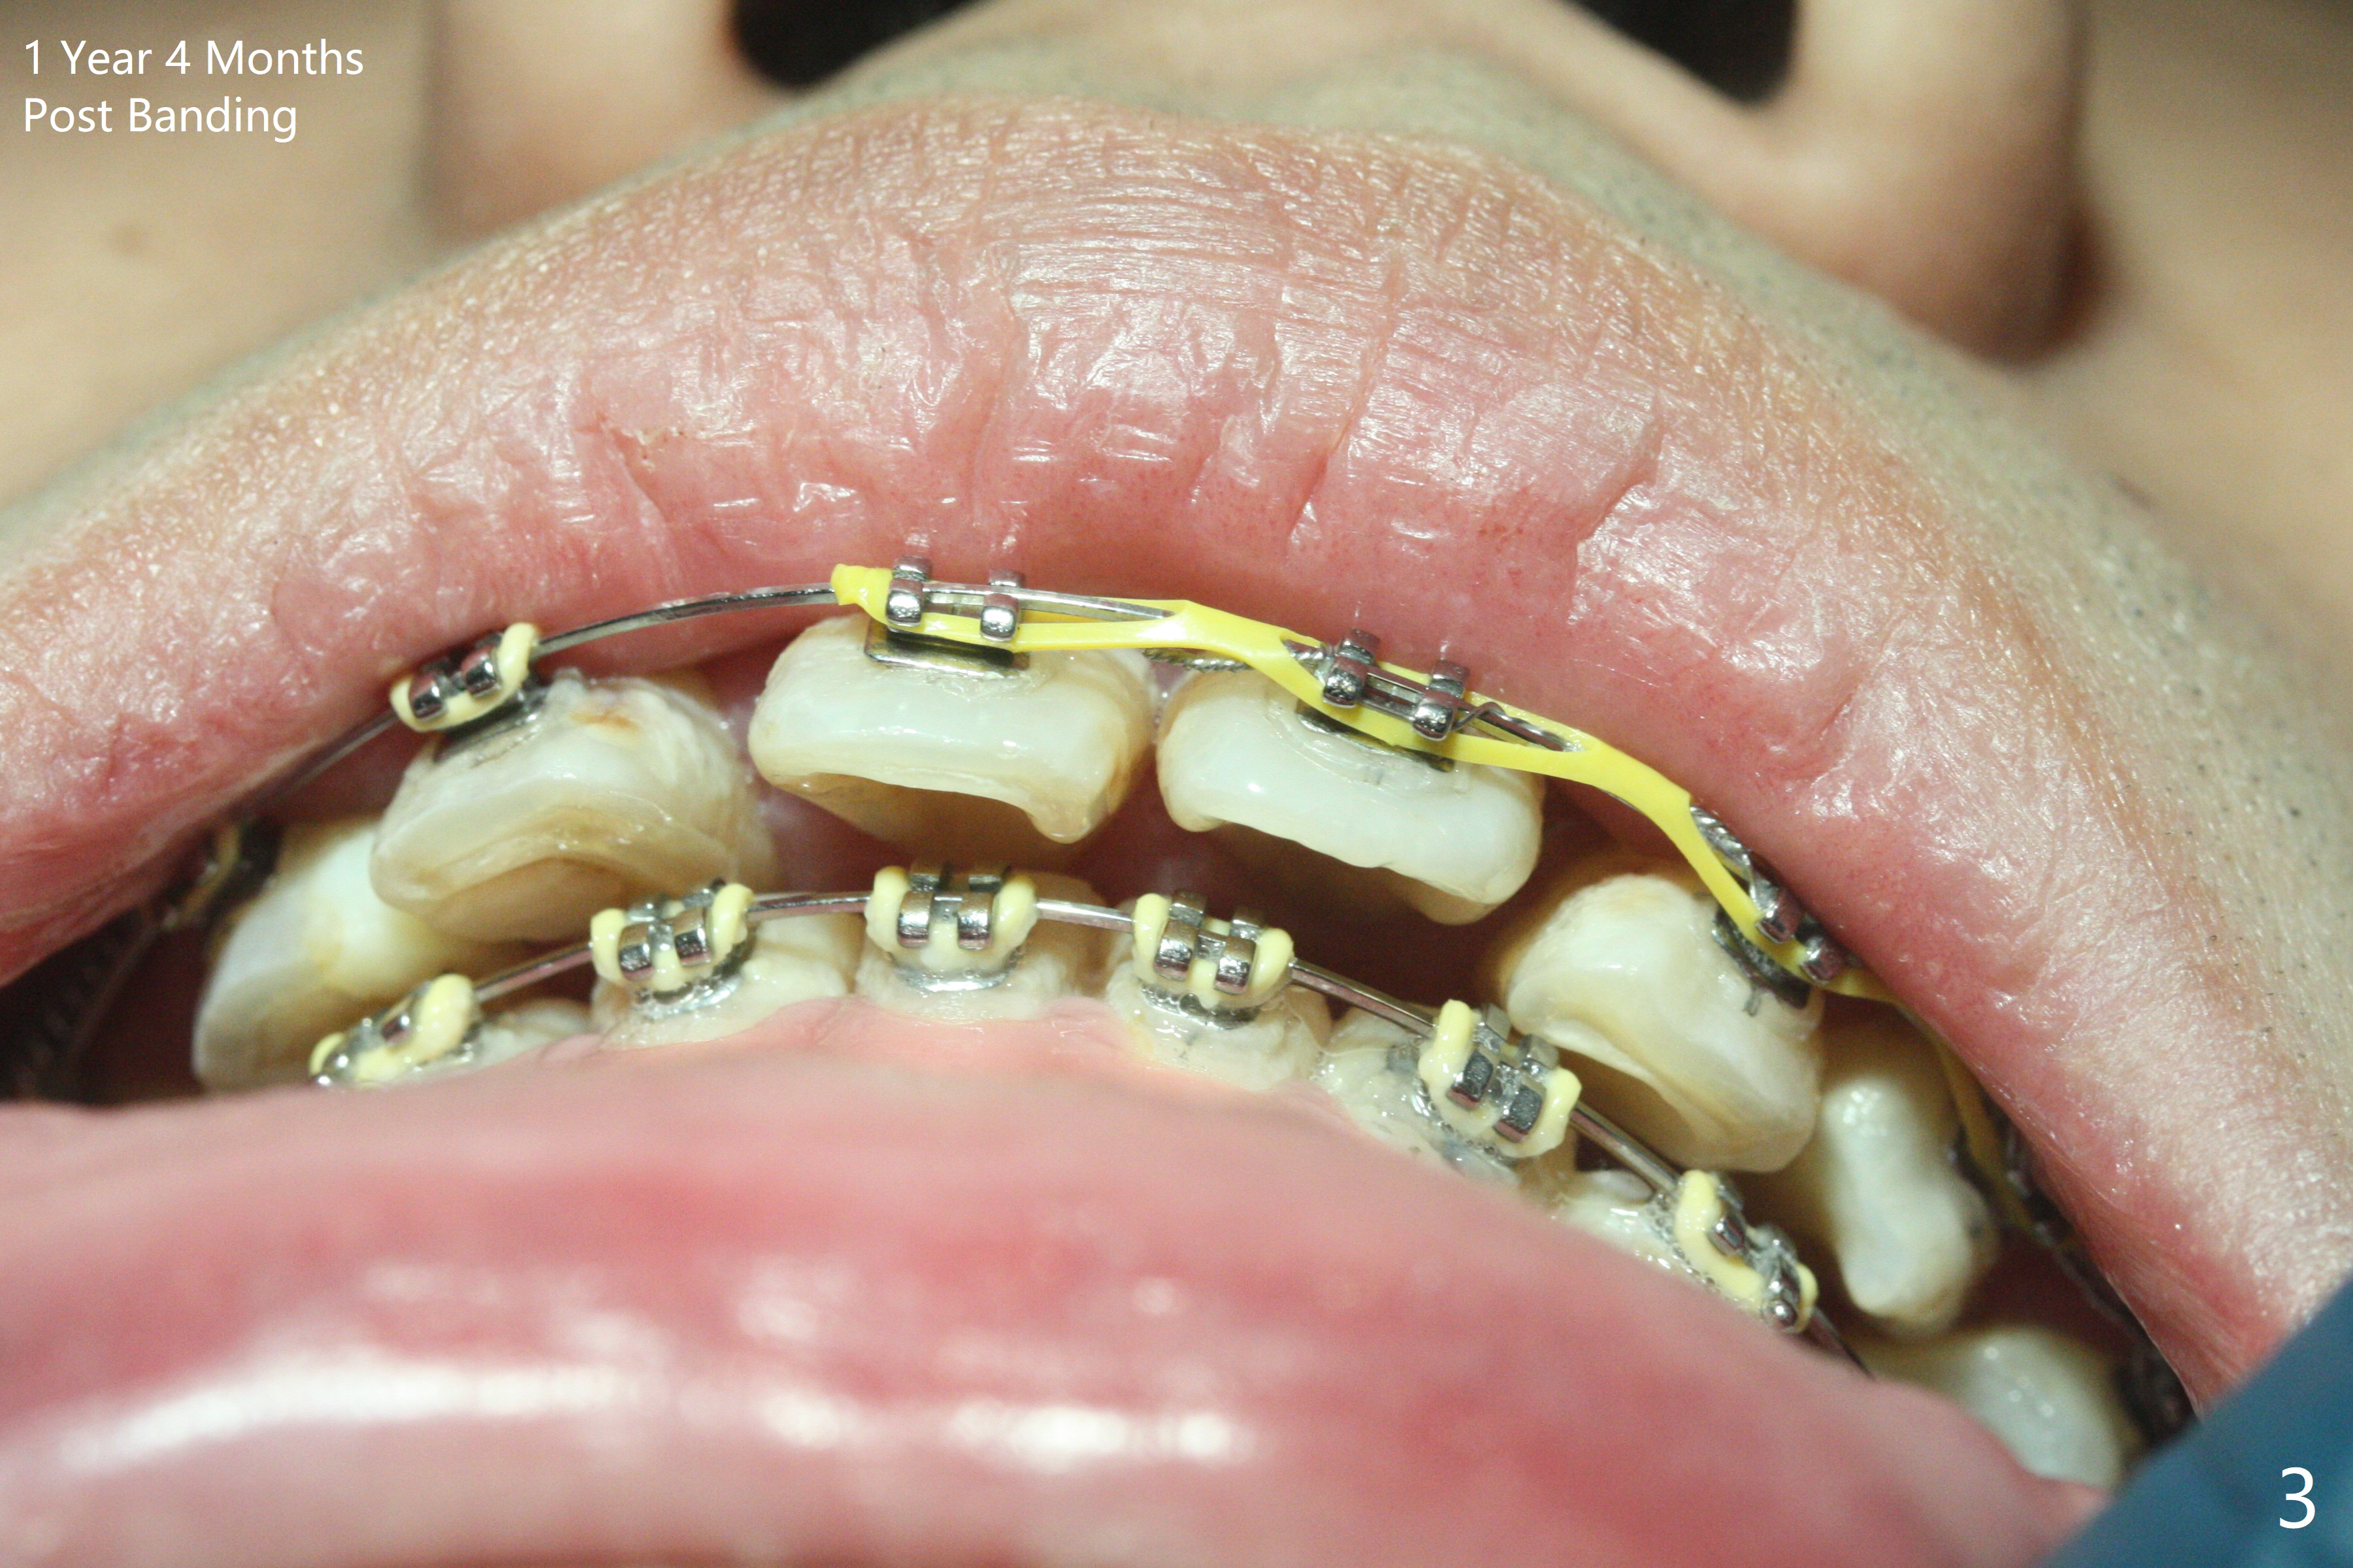

One year 4 months post banding (M) with 16x16 wires, UR3 is being distalized using UR7 as anchor (Fig.1), while the upper dental midline matches the facial one (Fig.2). The anterior overjet remains large (Fig.3). When UR3 is fully distalized, place posted wire to distalize U2-2 together. U2-2 distalization seems to be slow with one 16 mm closed coil spring each side (between 7 and post) 1 year 10 months post banding. Since the upper anterior PA shows mild root resorption at UR2 (Fig.4), a 14 mm closed coil spring is added each side (between 6 and post, Fig.5,6). LR6 has pain 2 years 2 months post banding (Fig.7). Debridement confirms non-salvageability; a 5x11.5 mm implant will be near the mesial root (Fig.8). Power chains for a month leads to closure of the gap between 3 and 4 (Fig.8-11). The space between 4 and 7 is 15 mm. A 12 mm 1st molar crown will be made, while the remaining 3 mm space will be closed by mesialization of 7 using 2 power posts mesial and distal to 6 and 7. Draw 2 tubes of blood. Make an incision to expose the mesial crest of 6.